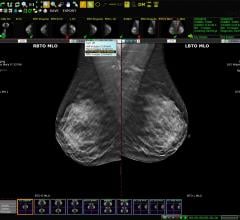

Despite decades of progress in breast imaging, one challenge continues to test even the most skilled radiologists ...